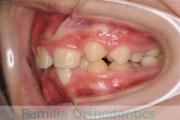

No.16V-139

- 叢生

- 16歳

- 男性

下の前歯が後ろにあるのが気になるとのことで来院されました。非抜歯で行うことも可能でしたが、上下左右から小臼歯抜歯をして治療を行うことをご希望になりました。

マルチブラケット法にて治療を行い、約3年、40回の通院が要でした。

かみ合わせが深い(上の前歯で下の前歯が覆われてしまう)ので、保定をしっかりしないと、また深くなってきてしまいやすいです。